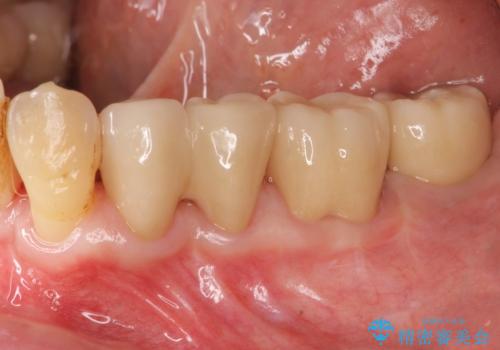

歯周ポケットの除去を併用したセラミック治療